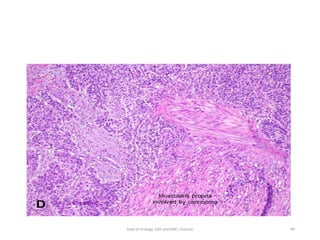

• Muscle invasive

• Histology:

• Invading urothelium shows irregular nests, single cell

infiltration or tentacular finger-like projections

• Stromal response

-desmoplasia,

-retraction or

-inflammation.

• Assess level of invasion for staging

.

• Presence and status of involvement of muscularis propria

should be reported in TURBT specimen for adequate staging.